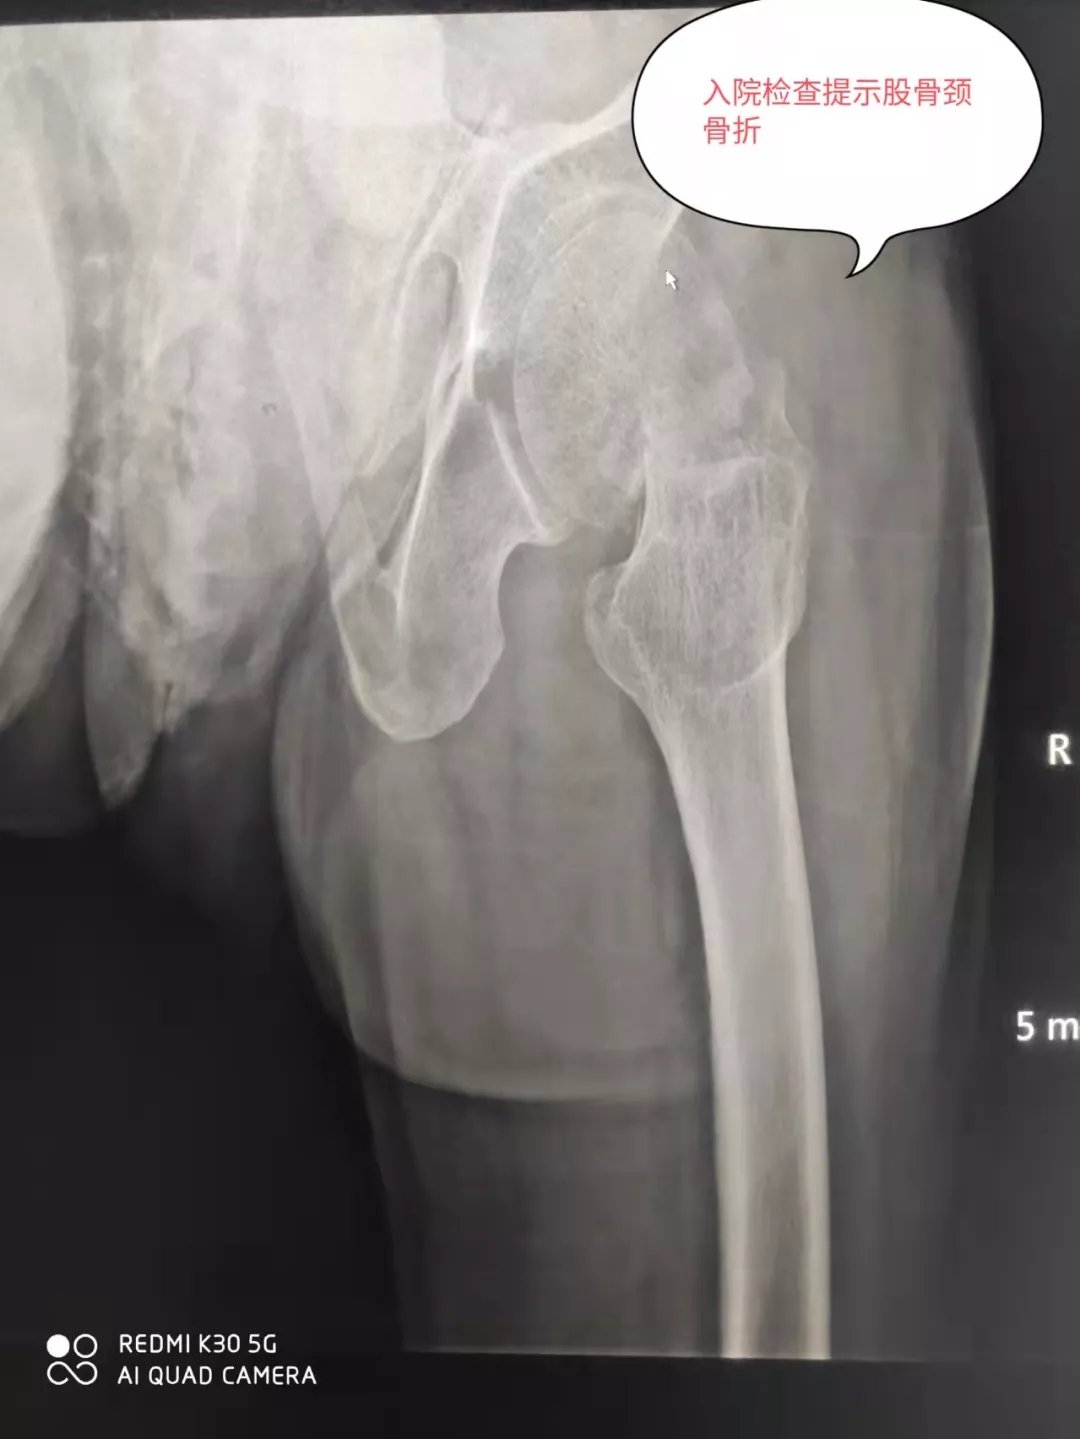

93岁的张爷爷不慎在家摔伤,左髋关节疼痛难忍,不敢活动,被家人紧急送至我院骨二科门诊就诊,检查提示左股骨颈骨折,入住骨二科治疗。

骨二科主管医生杨少洲接诊患者后,给予卧床制动,镇痛、补液、预防血栓等初步治疗。完善检查,评估患者的身体状况,经检查提示患者存在脑梗塞、脑积水、冠心病、缺血性心肌病、左前半束支传导阻滞、肾功能衰竭(代偿期)、贫血、电解质紊乱、高尿酸血症、骨质疏松等疾病。考虑患者年龄高、基础疾病多、手术风险大,告知患者家属病情及治疗方案和风险,经科室讨论后决定施行手术治疗,以便于患者早下床,减少卧床后的各种致命的并发症发生。请有关科室会诊后,骨二科为患者制定了详细周密的手术方案。凭借着丰富的临床经验和高水平创伤救治能力,在麻醉科的保驾护航下,骨二科团队用娴熟的手术技术,默契的团队配合,半小时内顺利完成左侧人工股骨头置换手术。术后24小时患者下床锻炼,1周后办理出院。